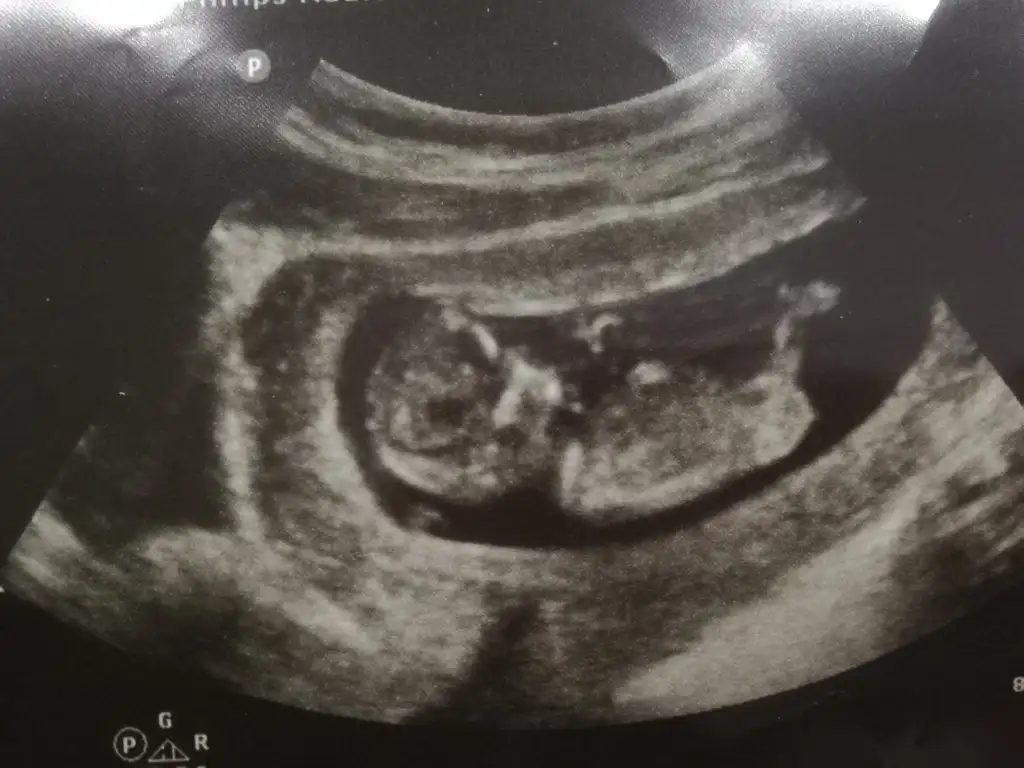

Merhaba Ikra meyra 10+4 CRL de 11+2 çıktı. Cinsiyet tahmininde bulunabilir misiniz?

• 3CA31E4C-82D2-40AE-A2AF-B9DA1AAD2F3F.webp

32,2 KB · Görüntüleme: 67